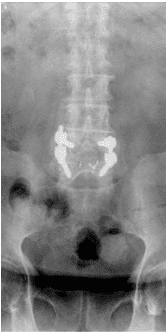

Patient underwent conservative management the problems using pain injections (Cortisone shots) and medications and achieved short term relief.